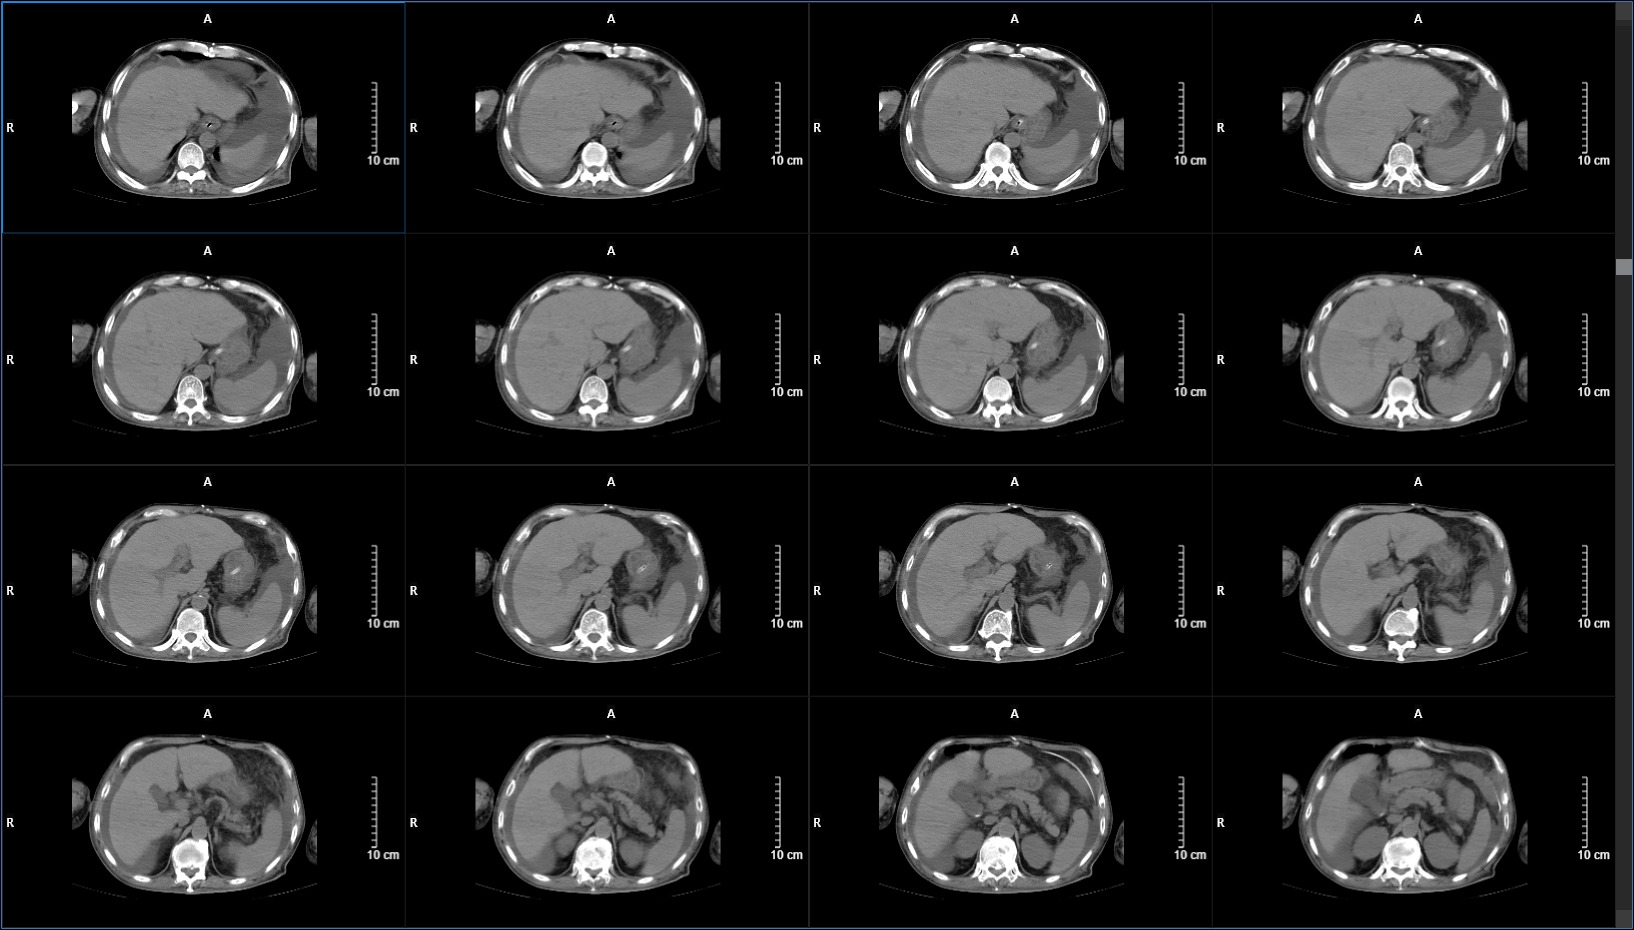

CT显示脑室饱满,颅压220mmH2O,行腰大池引流术,持续引流一周后(期间查脑脊液各项指标均正常),患者症状较入院时好转,查体能简单遵嘱动作,遂行脑室-腹腔分流术。